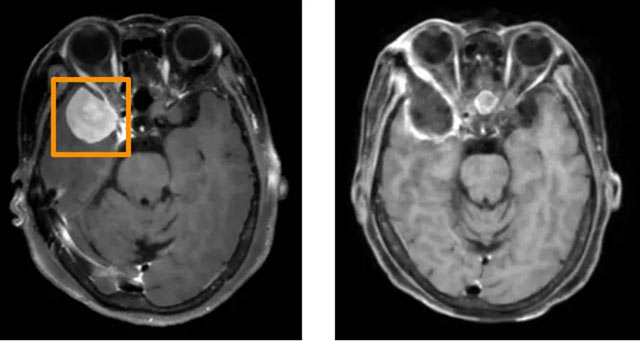

▲左图为术前MRI,术后MRI(右图)显示肿瘤已全切除

张女士因持续2个月的间歇性头痛,前往省医神经外科就诊。经检查发现,其右侧颞叶的脑膜瘤直径达3厘米,且已经迫邻近脑组织,如不及时进行手术治疗,患者可能会面临出现眼球运动障碍,甚至失明的风险。

“患者的肿瘤位于颞极,邻近视神经和颅内颈内动脉等大血管,传统开颅手术风险较高。”省医神经外科主任、学术带头人万锋介绍,传统开颅手术需大切口、剥离颞肌、广泛牵拉脑组织,可能导致神经功能损伤。

术中,治疗团队通过眉弓和眶缘仅5厘米内的微小切口建立手术通道,结合神经内镜与显微操作,实现肿瘤全切。术后,张女士恢复良好,无并发症,手术疤痕隐藏于眉毛之下。